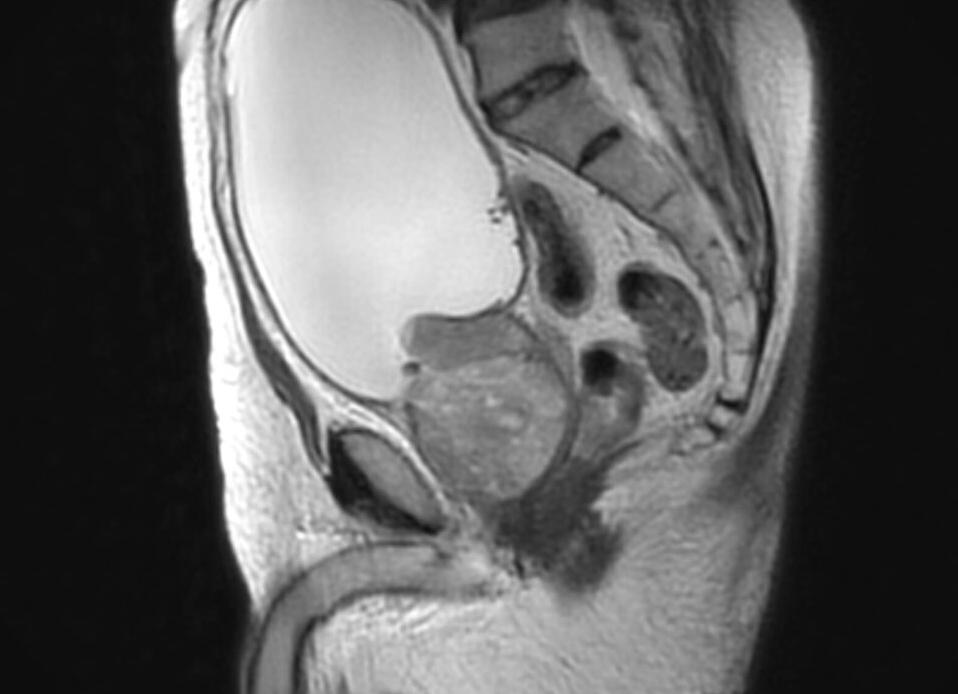

Мрт таза у мужчин

МРТ малого таза у мужчин: выявление труднораспознаваемых заболеваний

МРТ органов малого таза у мужчин в своем развитии всего за два десятка лет вышло на лидирующие позиции в области диагностирования трудно распознаваемых мужских заболеваний. Особенно следует отметить среди них те, для которых характерно слишком позднее проявление типичной симптоматики. Заболевания, относящиеся к патологиям органов малого таза, легко распознаются при помощи технологии МРТ.